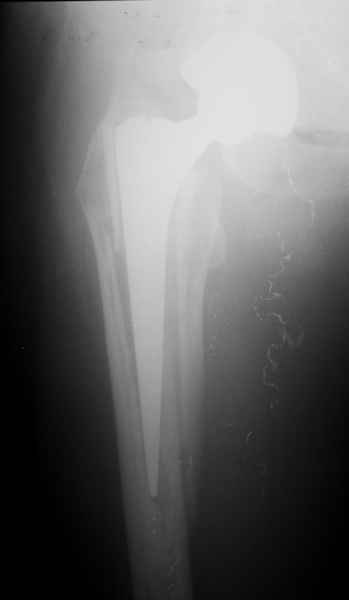

Можно уверенно рассчитывать на сращение фрагментов бедра между собой. Можно ли рассчитывать на реинтеграцию имеющейся ножки в проксимальном отделе - действительно вопрос открытый. Но во всяком случае ножка будет заметное время стабильной за счет дистальной фиксации. Будет ли это время достаточно на всю оставшуюся жизнь пациента - трудно предугадать.

Но, как Александр Виноградский справедливо заметил, после сращения бедра появляется возможность поставить даже обычную ножку большего размера.

2. Применение ножки дистальной фиксации, мы отдаем предпочтение ножке Вагнера с фиксацией проксимального отдела на ножке. Более травматичное вмешательство, но при стабильной фиксации ножки реабилитация идет в обычном режиме.

Хочется показать два подобных случая, П-ка З. 72 лет и п-т Г. 80 лет. Сразу принимаю замечание, что это были ножки цементной фиксации, просто под руками не было бесцементника.